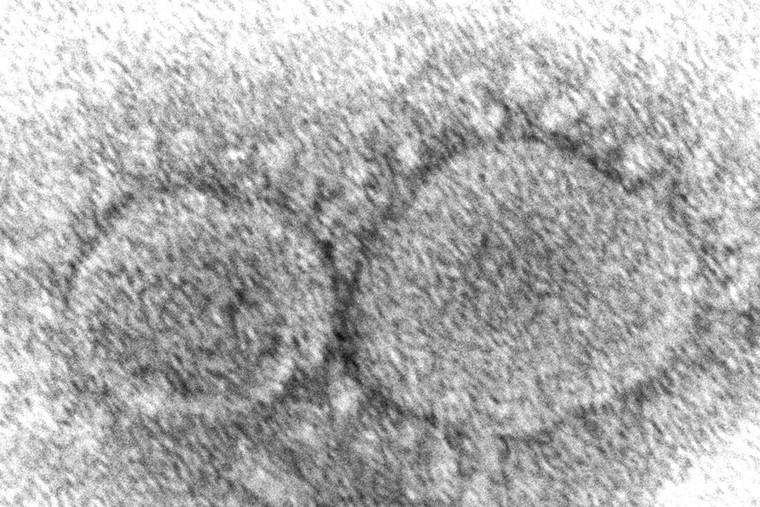

WHO cảnh báo Omicron đang lây lan nhanh hơn bất kỳ biến thể nào khác và "chỉ riêng vaccine sẽ không giúp quốc gia nào thoát khỏi cuộc khủng hoảng này". Ảnh: CNN |

| Hình ảnh biến thể virus Omicron dưới kính hiển vi. |